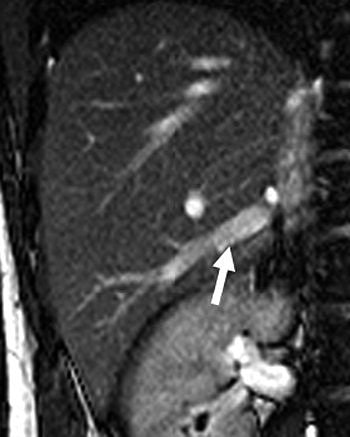

![]() |

| Twenty-year-old man with large right inferior accessory hepatic vein. Balanced turbo field-echo images (above, axial image; below, coronal image) reveal a 7.3-mm right inferior accessory hepatic vein (arrow) entering inferior vena cava. Lim JS, Kim M, Kim JH, Kim SI, Choi J, Park M, Oh YT, Yoo HS, Lee JT, Kim KW, "Preoperative MRI of Potential Living-Donor-Related Liver Transplantation Using a Single Dose of Gadobenate Dimeglumine" (AJR 2005;185:424-431). |